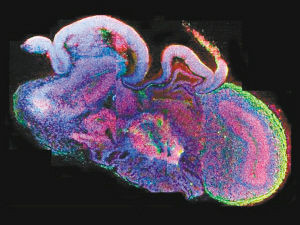

研究人員利用特別搭配的多種營養物質,促使幹細胞生長並組成複雜結構,以此培養出可以形成腦和神經系統的神經外胚層。神經外胚層組織碎片被放置在一個旋轉生物反應器內,在有氧氣循環和養分供給的環境下逐漸形成“類腦器官”。

開始培養一個月後,神經外胚層碎片組成視網膜、脈絡叢和大腦皮層等大腦組成部分。兩個月後,“迷你人腦”長成,儘管大小僅4毫米,結構細密程度難以與發育完成的人腦相比,卻擁有能夠放電的神經元和多種腦神經組織。

迷你人腦問世標誌著科學家首次成功以三維形式複製人腦組織形成過程。